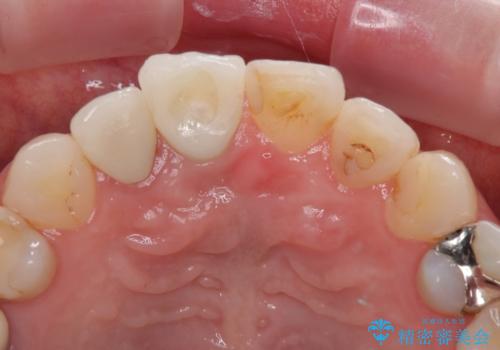

- 前歯のセラミッククランが外れてしまったとのことで来院された患者様です。

診察をしたところ、歯根に縦破折が認められ、抜歯が必要と判断されました。

抜歯、インプラント埋入、仮歯の装着が同時に可能な1DAYインプラントが適用可能と判断されたため、インプラントによる補綴治療を行うこととしました。